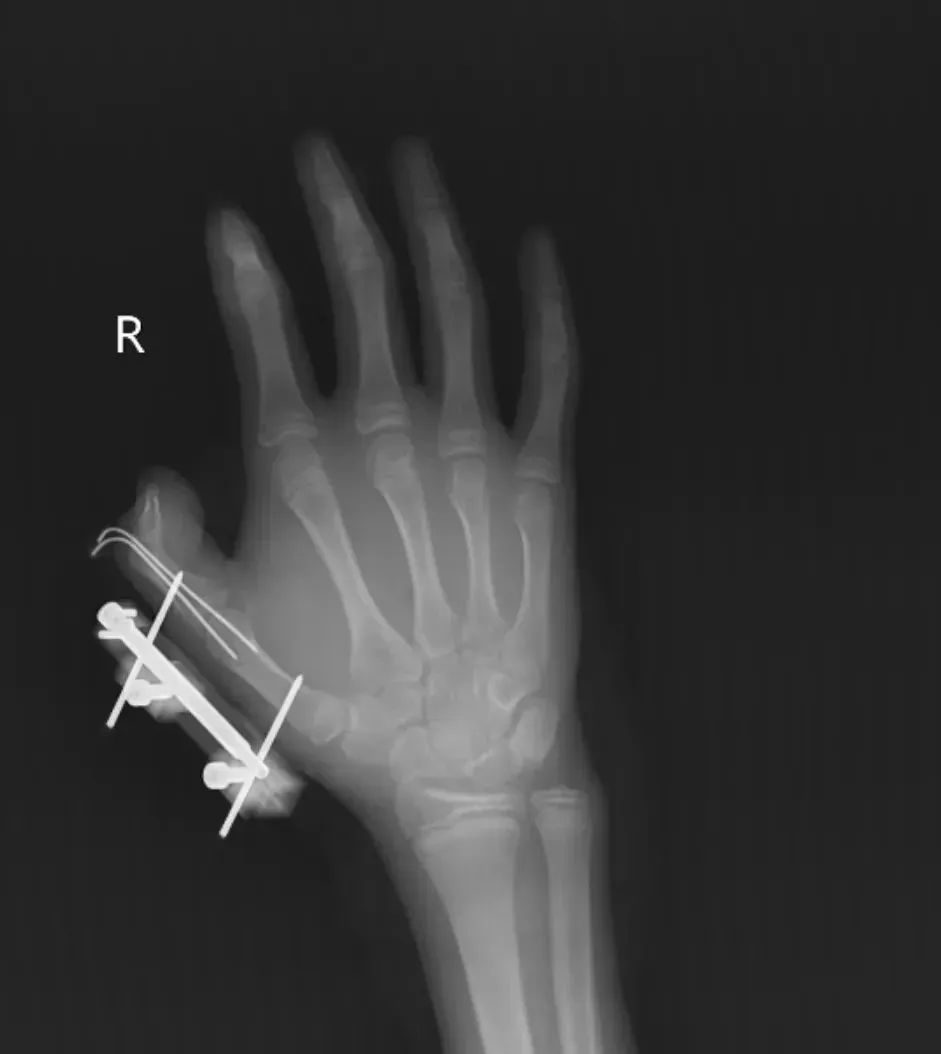

14岁少年手指被炸伤

维维的右手瞬间鲜血直流

拇指虎口处

被撕开一道约10厘米的伤口

肌肉组织断裂外露

还伴随拇指骨折、关节脱位

整个拇指完全失去知觉

经治疗

维维的拇指保住了

但后续还需长期康复训练

才能慢慢恢复手部精细动作功能